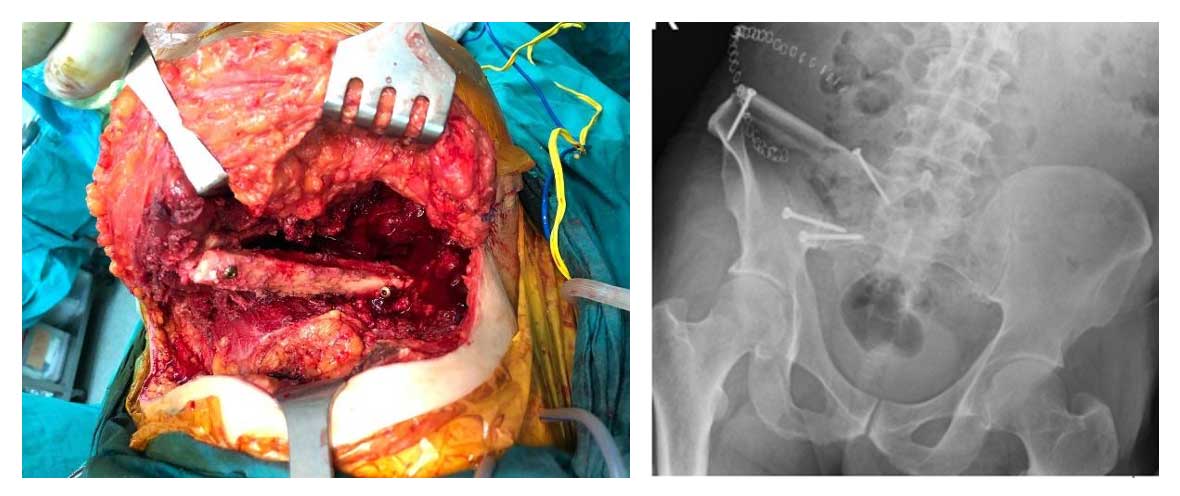

Hastanın leğen kemiğinde yer alan tümörlü bölge tek parça halinde çıkarılmıştır. Oluşan kemik boşluğu, aynı bacaktan alınan fibula kemiğiyle (otogreft transferi) doldurulmuş ve titanyum vidalar ile sabitlenmiştir. Bu işlem sayesinde hem stabilite sağlanmış hem de biyolojik iyileşme desteklenmiştir.

Ameliyat Esnası ve Sonrası: Kemiğin tümörlü kısmı çıktıktan sonra fibula kemiğinin araya yerleştirilmesi ve vidalar ile sabitlenmesi görülmekte.